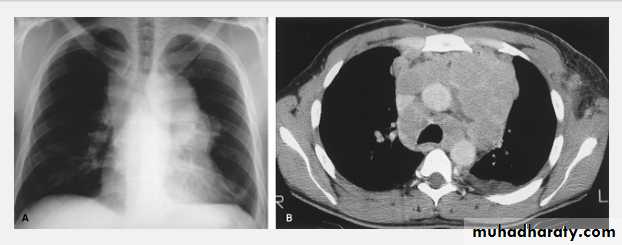

Thymoma.

A chest x-ray (A) reveals an unusual contour over the left hilum (arrows). That the hilum is not obscured (no silhouette sign) indicates that the mass must either be in front of or behind the hilum. A computed tomography scan (B) reveals a soft tissue mass (arrow) just to the left of the aorta. This is the most common location of a thymoma.Mediastinal teratoma. A chest x-ray (A) shows a large upper right mediastinal mass (arrows), but no specific internal structure is apparent. A computed tomography scan (B) reveals that the mass contains multiple types of tissue elements including fat (dark), soft tissue (gray), and calcium (white). This is essentially diagnostic of a teratoma.